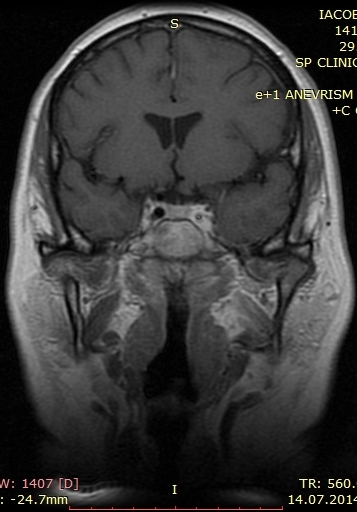

A new case of a 50-year-old female who presented with left otorrhagia caused by an internal carotid aneurysm is reported. No medical history of tinnitus, vertigo, otalgia or otorrhea. Middle ear surgery was effective in resolving bleeding and did not cause any permanent neurological deficit. High resolution computed tomography angiography is the technique of choice and, in some cases, can be complemented with a magnetic resonance angiography. Misdiagnosis of the internal carotid artery aneurysm may lead to serious morbidity because of bleeding or vascular occlusion.